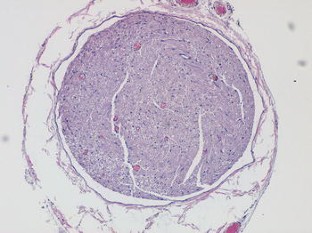

The purpose of the current study was to establish a valid protocol for nerve cryopreservation, and to evaluate if the addition of albumin supposed any advantage in the procedure. We compared a traditional cryopreservation method that uses dimethyl sulfoxide (DMSO) as cryoprotectant, to an alternative method that uses DMSO and albumin. Six Wistar Lewis rats were used to obtain twelve 20 mm fragments of sciatic nerve. In the first group, six fragments were cryopreserved in 199 media with 10% DMSO, with a temperature decreasing rate of 1 °C per minute. In the second group, six fragments were cryopreserved adding 4% human albumin. The unfreezing process consisted of sequential washings with saline in the first group, and saline and 20% albumin in the second group at 37 °C until the crioprotectant was removed. Structural evaluation was performed through histological analysis and electronic microscopy. The viability was assessed with the calcein-AM (CAM) and 4′,6-diamino-2-fenilindol (DAPI) staining. Histological results showed a correct preservation of peripheral nerve architecture and no significant differences were found between the two groups. However, Schwann cells viability showed in the CAM-DAPI staining was significantly superior in the albumin group. The viability of Schwann cells was significantly increased when albumin was added to the nerve cryopreservation protocol. However, no significant structural differences were found between groups. Further studies need to be performed to assess the cryopreserved nerve functionality using this new method.